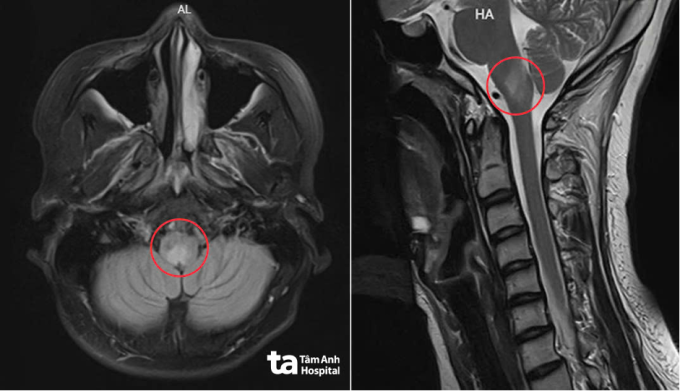

Kết quả chụp MRI 3 Tesla cho thấy các tổn thương viêm tại hành não, vùng hạ đồi quanh thành não... Tổn thương phân bố dọc trục thần kinh trung ương nên bác sĩ loại trừ nguyên nhân đột quỵ hay khối u. Nhi được chỉ định xét nghiệm kháng thể kháng Aquaporin-4 (AQP4-IgG) trong huyết thanh, kết quả dương tính.

Ảnh MRI 3 Tesla cho thấy các tổn thương của Nhi phân bố dọc trục thần kinh trung ương. Ảnh: Bệnh viện Đa khoa Tâm Anh

Các kết quả cho thấy người bệnh bị viêm tủy thị thần kinh. Bác sĩ Tiên giải thích đây là bệnh tự miễn, xảy ra khi hệ miễn dịch của cơ thể "nhận nhầm" một số cấu trúc của hệ thần kinh trung ương là tác nhân lạ và tạo kháng thể tấn công. Đích tấn công là protein Aquaporin-4 - một kênh dẫn nước nằm dày đặc trên tế bào thần kinh đệm, có vai trò điều hòa cân bằng nước, bảo vệ tế bào thần kinh. Phản ứng này kích hoạt viêm mạnh, làm tổn thương tế bào thần kinh đệm, phá vỡ hàng rào bảo vệ thần kinh, gây phù nề, hoại tử mô. Quá trình thường xảy ra tại dây thần kinh thị giác, tủy sống, thân não, những vùng tập trung nhiều Aquaporin-4, khiến người bệnh xuất hiện mờ mắt, yếu liệt, rối loạn thăng bằng hoặc nấc cụt, buồn nôn kéo dài.